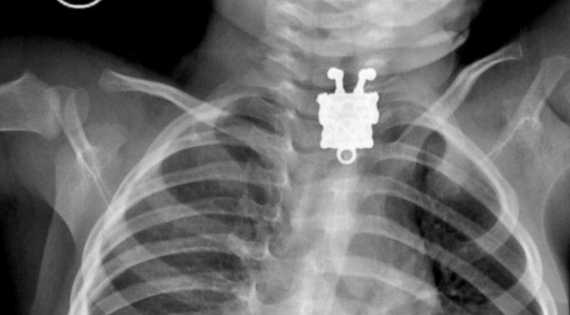

Le hacen una radiografía y encuentran un cuchillo en el pecho que llevaba un año ahí

La sorpresa no fue menor tanto en el joven como en los empleados del laboratorio que con asombro observaron el resultado médico. Al mostrarle la placa que le acababan de realizar, Kent Ryan Tomao lo entendió todo: se podía ver perfectamente el filo de un cuchillo en su pecho. Pero no se trataba de un cuchillo pequeño, sino que era de grandes dimensiones.

Kent Ryan Tomao ha señalado que se quedó tan sorprendido como los médicos por el tamaño del cuchillo que había en su interior, aunque él notaba algo raro: "Siempre me pregunté por qué sentía algo de dolor en mi pecho cuando hacía frío, pero no tenía idea de que aquel cuchillazo seguía ahí dentro de mi cuerpo".

El joven tendrá que regresar en breve al hospital de Kidapawan, en Filipinas, para ser intervenido nuevamente y poder extraerle el cuchillo. Mientras, asegura que no piensa denunciar a los médicos que le operaron un año atrás por su negligencia ya que, durante este tiempo, apenas le ha afectado a su vida.